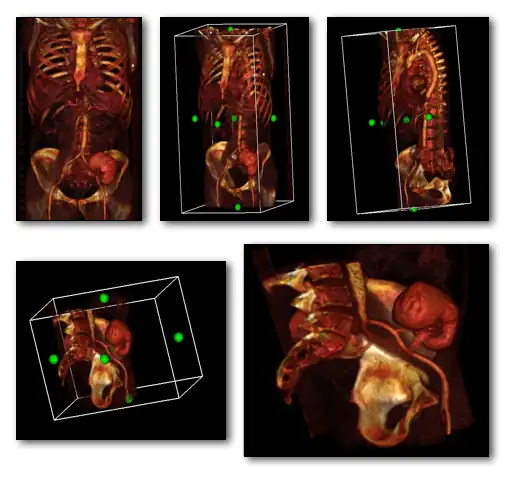

- A final variant on the MPR theme is the generation of a three-dimensional display showing all three orthogonal projections combined so that a defined point of interest locates the intersection of the planes, as illustrated in Figure 5.22.

- The point of intersection is located for illustrative purposes at the centre of the voxel data in the figure. It can typically be placed at any point in the 3D data using interactive controls. In addition, the perspective used for the rotating sequence can be manipulated interactively to improve the visualization of a region of interest. Note that the image sequence illustrated is one from a myriad of perspectives that can thus be generated. Note also that slice projections (e.g. MIPs) can be combined with this form of display to provide additional perspectives on a feature of interest.